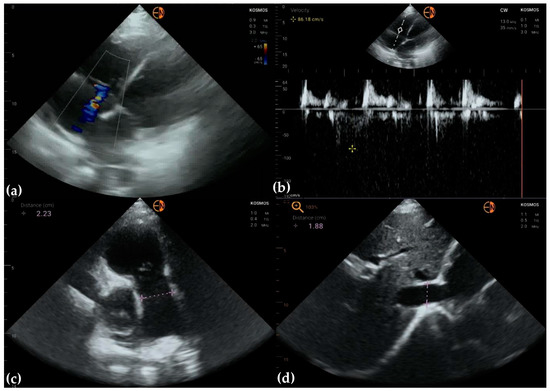

3.2. Measurements of Cardiovascular Structures

3.3. Valvular Stenosis and Regurgitation